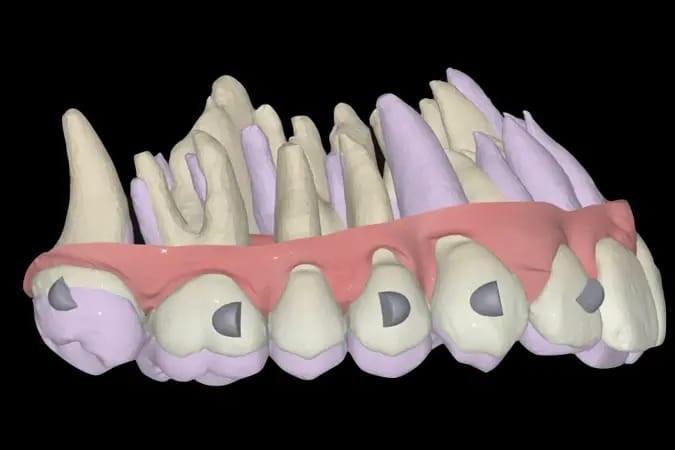

Более того, окончательная крепление виртуального артикулятора продемонстрировало точное соответствие между максимальной интеркуспацией пациента и истинной дугой смыкания. Такое выравнивание отражает достижение ортопедической стабильности — непременного условия для долгосрочного здоровья зубов, функционального прикуса и стабильности результатов лечения (фото 16).

Фото 16a–c: Крепление виртуального артикулятора с помощью MODJAW, демонстрирующее ортопедическую стабильность.